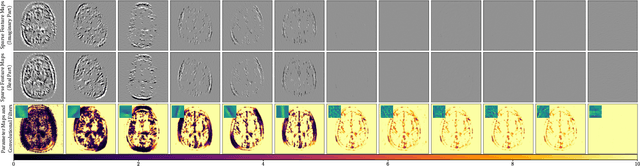

Abstract:We propose an unrolled algorithm approach for learning spatially adaptive parameter maps in the framework of convolutional synthesis-based $\ell_1$ regularization. More precisely, we consider a family of pre-trained convolutional filters and estimate deeply parametrized spatially varying parameters applied to the sparse feature maps by means of unrolling a FISTA algorithm to solve the underlying sparse estimation problem. The proposed approach is evaluated for image reconstruction of low-field MRI and compared to spatially adaptive and non-adaptive analysis-type procedures relying on Total Variation regularization and to a well-established model-based deep learning approach. We show that the proposed approach produces visually and quantitatively comparable results with the latter approaches and at the same time remains highly interpretable. In particular, the inferred parameter maps quantify the local contribution of each filter in the reconstruction, which provides valuable insight into the algorithm mechanism and could potentially be used to discard unsuited filters.